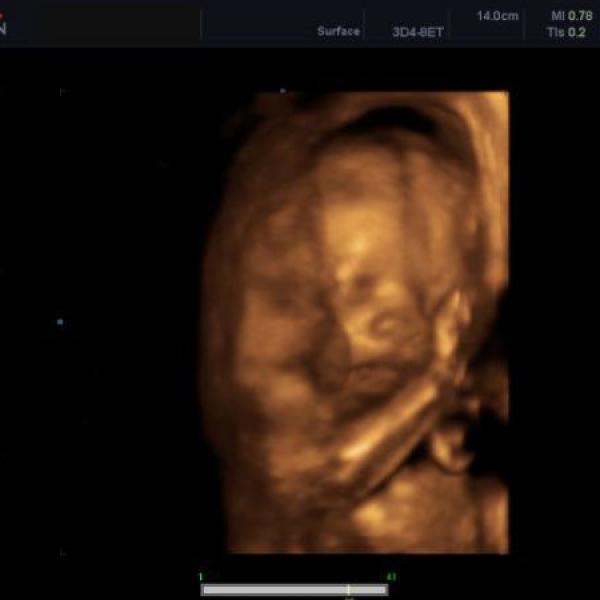

Ahojky spolutěhulky :) tak máme dneska za sebou 3D ultrazvuk - Kubík se vrtěl o sto šest, tak bylo těžký ho vyblejsknout - nakonec se z CDčka dá vybrat tak 5 fotek, jednu přikládám - má